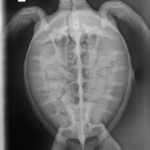

9.1 lbs. non-FP juvenile green

Hook in left front flipper and moderate abrasions on plastron and on all flippers.

In-house PCV = 36%, TP = 3.8 g/dl, glucose = 89. Started on Ceftaz, Vitamin B, and Normosol.